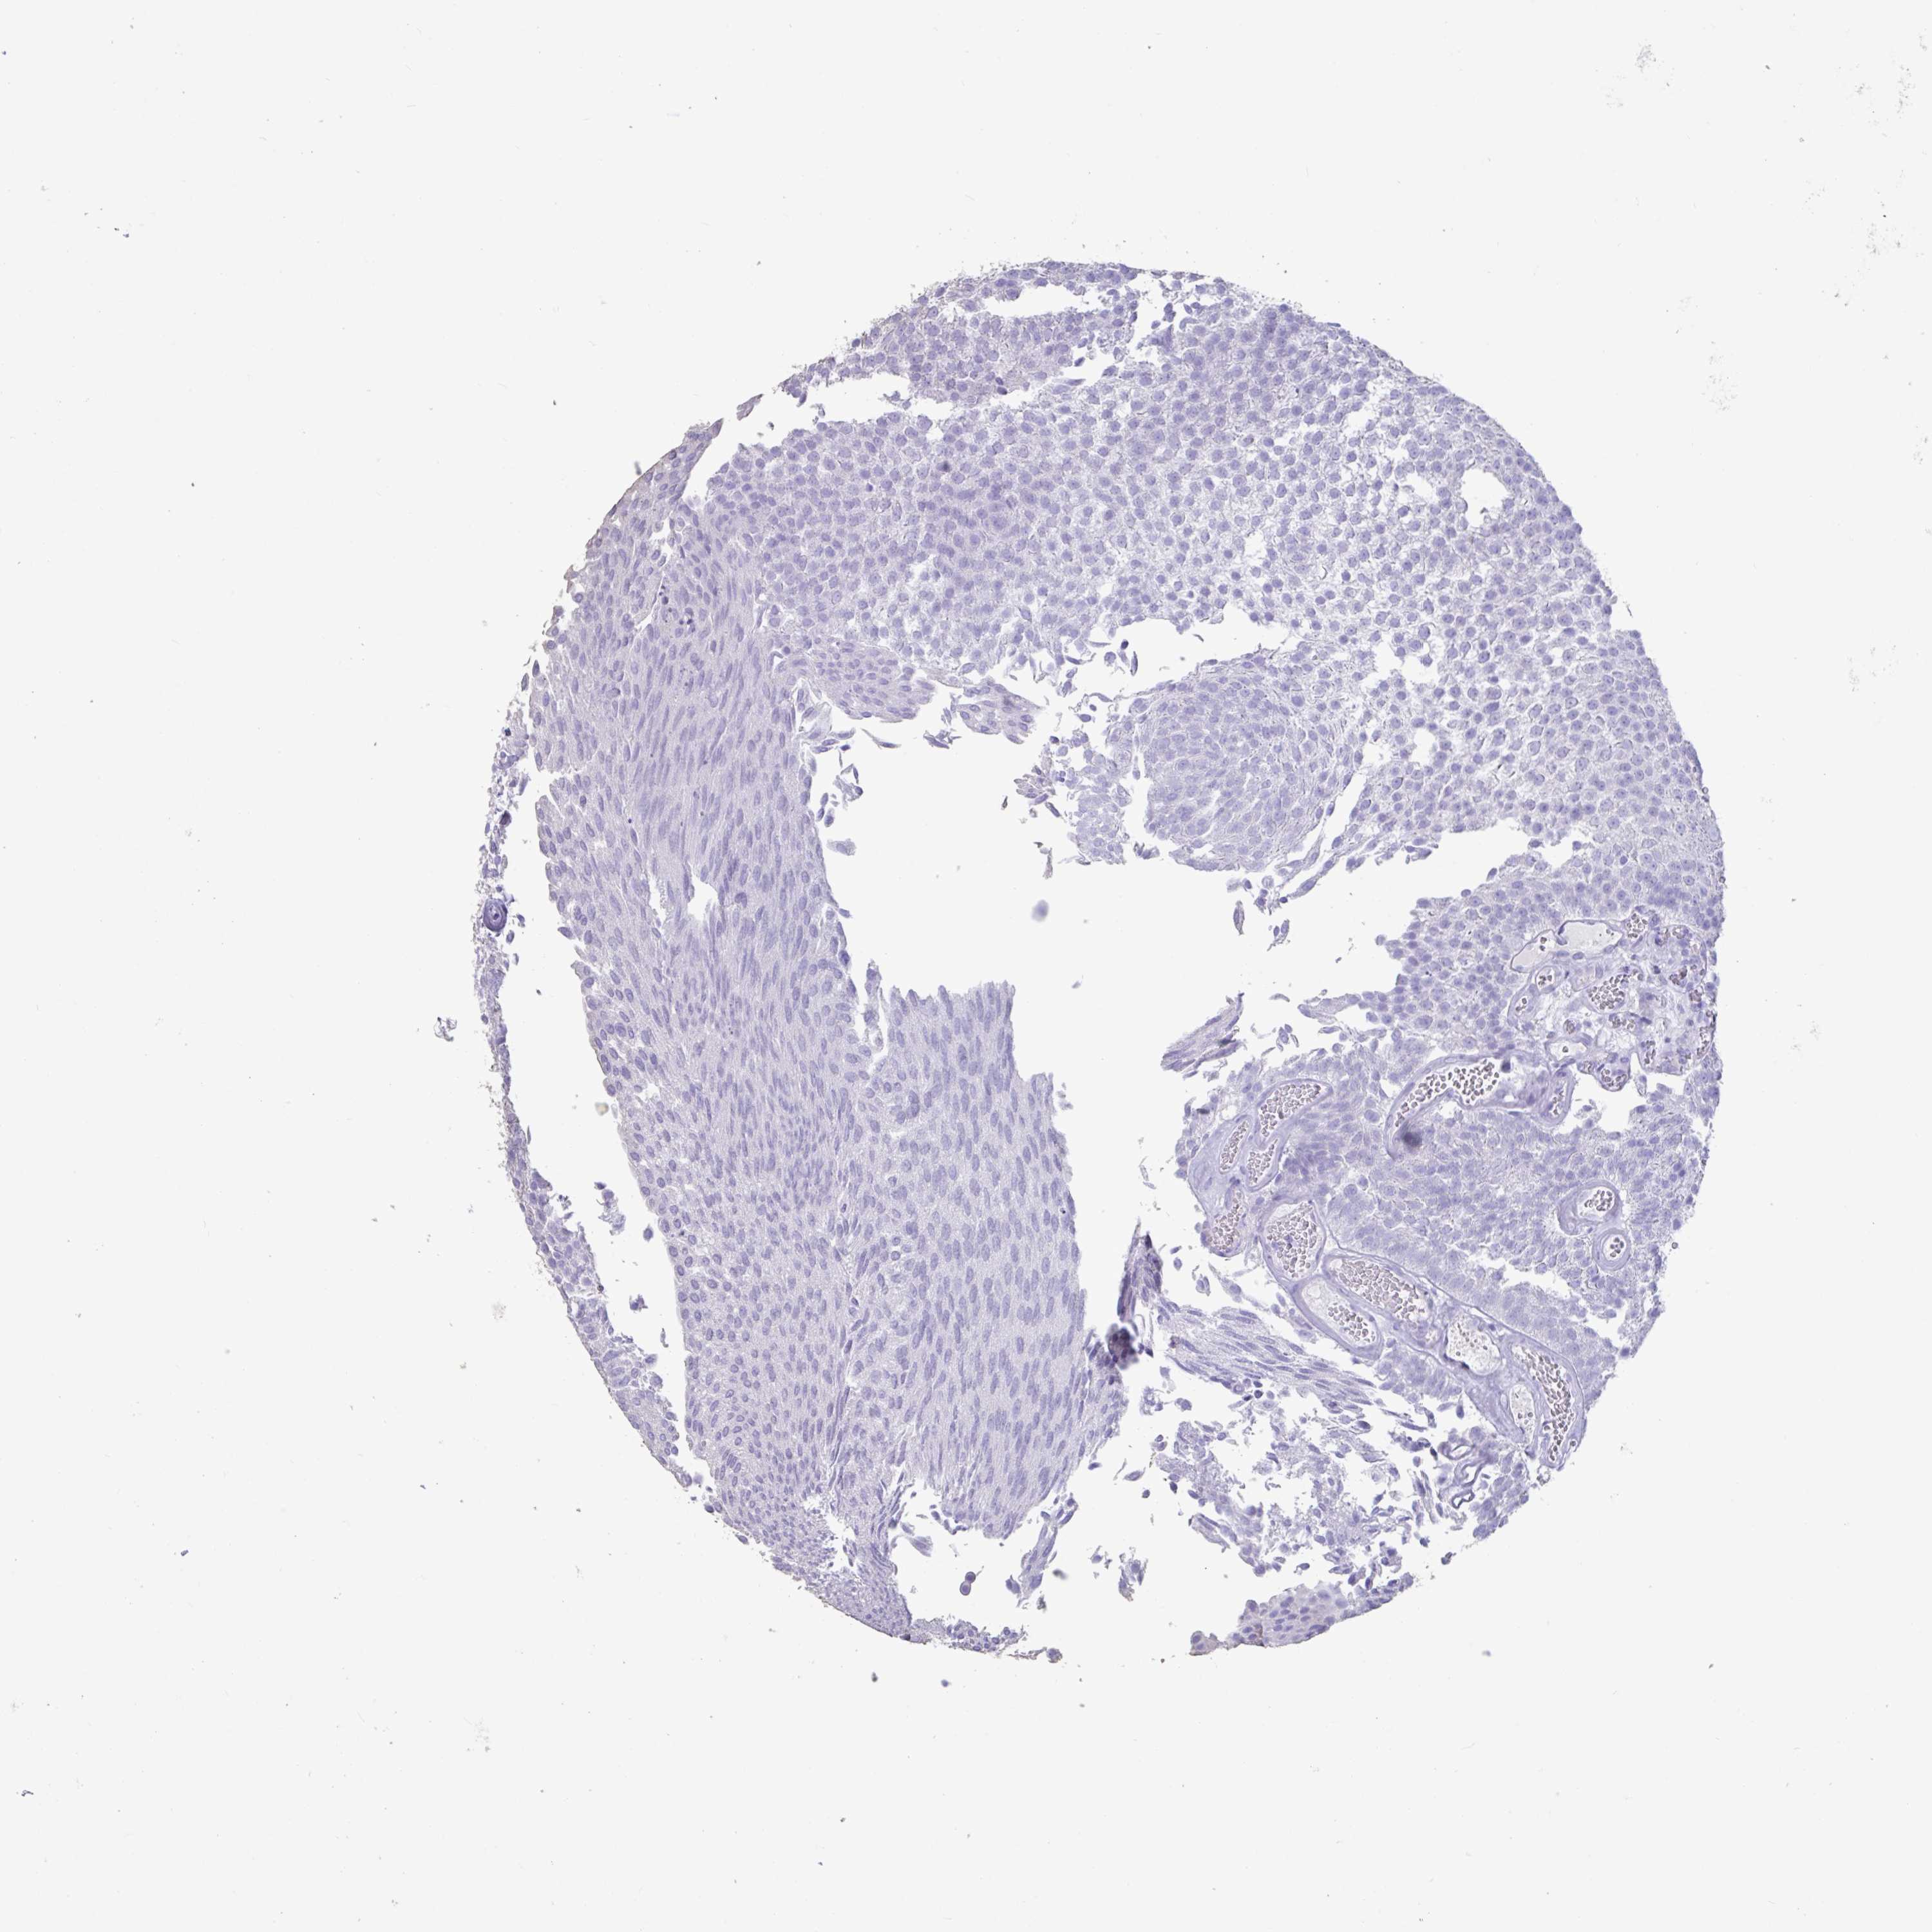

UROTHELIAL CANCER - Protein expressioni

A mouse-over function shows sample information and annotation data. Click on an image to view it in a full screen mode. Samples can be filtered based on level of antibody staining by selecting one or several of the following categories: high, medium, low and not detected. The assay and annotation is described here.

Note that samples used for immunohistochemistry by the Human Protein Atlas do not correspond to samples in the TCGA dataset.

Antibody stainingi

Antibody staining in the annotated cell types in the current human tissue is reported as not detected, low, medium, or high, based on conventional immunohistochemistry profiling in selected tissues. This score is based on the combination of the staining intensity and fraction of stained cells.

Each image is clickable and will lead to virtual microscopy that enables deeper exploration of all samples and also displays staining intensity scores, fraction scores and subcellular localization as well as patient and tissue information for each sample.

Antibody HPA044848

Antibody HPA056897

Antibody CAB002450

Staining

High

Medium

Low

Not detected

Intensity

Strong

Moderate

Weak

Negative

Quantity

>75%

75%-25%

<25%

None

Location

Nuclear

Cytoplasmic/membranous

Cytoplasmic/membranous,nuclear

Urothelial carcinoma, High grade

Urothelial carcinoma, NOS

Urothelial carcinoma, Low grade

Adenocarcinoma, NOS